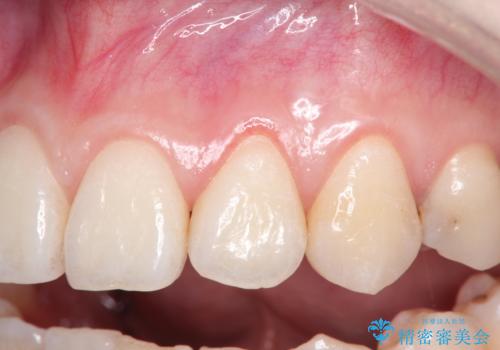

前歯の歯肉退縮 歯周形成外科(歯冠側移動術)